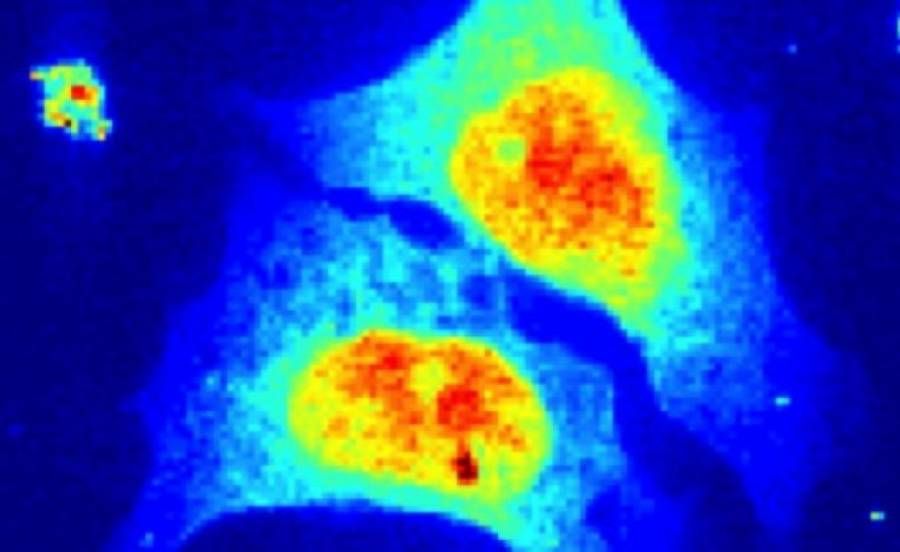

Επιστήμονες από το Πανεπιστήμιο του Γκότινγκεν ανέπτυξαν μια μέθοδο, που τους επιτρέπει να «βλέπουν» εντός των κυττάρων, ενόσω αυτά βρίσκονται στη φυσική κατάστασή τους και δημιούργησαν την πρώτη ακτινογραφία μεμονωμένου καρκινικού κυττάρου.

Η νέα μέθοδος επιτρέπει, για πρώτη φορά, τη μελέτη των εσωτερικών δομών ζωντανών κυττάρων, ενώ αυτά βρίσκονται σε –σχεδόν- φυσικό περιβάλλον με τη χρήση ακτίνων Χ, παράγοντας τόσο ευκρινείς εικόνες, ώστε οι δομές να είναι ορατές σε κλίμακα νανομέτρου.

Μάλιστα, η σύγκριση μεταξύ της ανάλυσης των ζωντανών κυττάρων και των κυττάρων που είχαν υποστεί χημική επεξεργασία, έδειξε ότι η χημική μέθοδος προκαλεί μεγάλες αλλαγές στις μικροσκοπικές δομές εντός των κυττάρων.